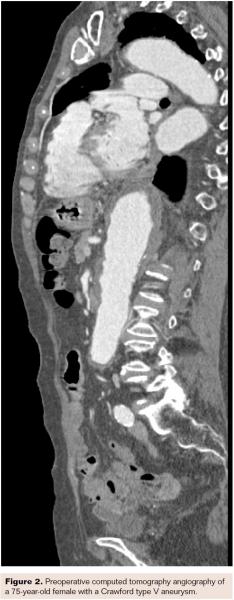

In the first patient-level meta-analysis of the SMFM, the authors established a 2.9% 30-day mortality rate with the SMFM when used in patients with complex thoracic aortic pathology. This outcome is superior to mortality demonstrated with other treatment modalities for similar pathology.31 Furthermore, there were no incidences of paraplegia, stroke, or renal failure. If the SMFM is used within the IFU, these outcomes persist with an aneurysm-related survival rate of 93.3% at 18 months.31 Figures 2-4 show a successful intervention in a 75-year-old female patient with a Crawford type V aneurysm. The patient was successfully treated with 3 SMFM devices.